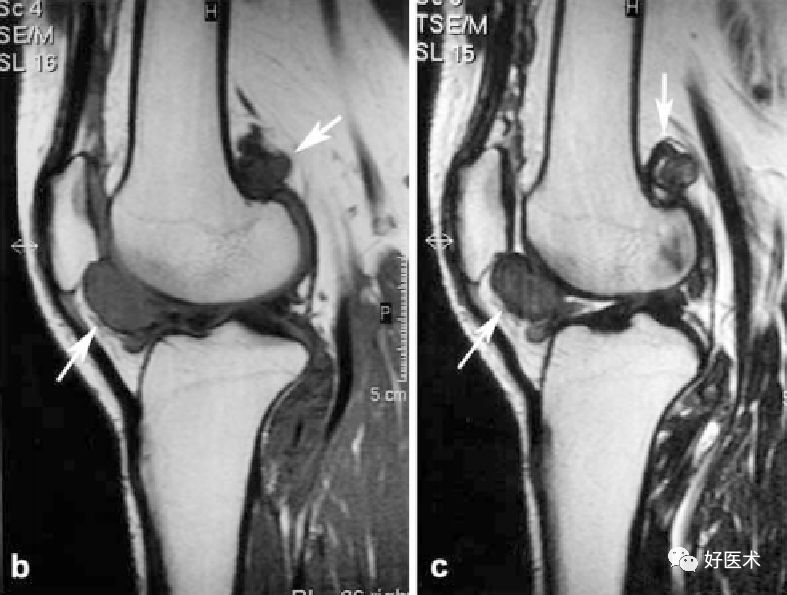

MRI表现

MRI对膝关节PVS具有定性诊断意义,它可以清楚显示病变的范围、关节软骨及骨质破坏的程度,其特征性表现为T1、T2加权像时低密度信号区。故MRI已成为X线片检查后首选的影像学检查方法。术前MRI检查不仅有助于明确关节内、外病变程度和范围,同时,术后MRI检查也是检查病变复发与否的最敏感手段。

髌下脂肪囊及关节腔滑膜呈绒毛、结节样隆起,并可见形态不规则T1、T2双低信号含铁血黄素沉着,关节积液

滑膜弥漫增厚,髌上囊、髌下脂肪囊及关节腔滑膜呈绒毛、结节样隆起,并可见形态不规则T1、T2双低信号含铁血黄素沉着,关节积液